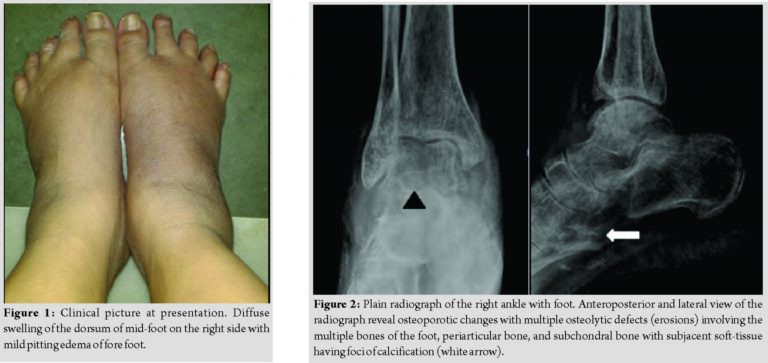

On presentation to our institute, there was diffuse swelling of the dorsum of mid-foot with mild pitting edema of forefoot without any associated pain (Fig. 1). All movements of the toes and ankle were a normal without any neurovascular deficits. She was evaluated further with blood investigations which revealed a normal hemogram and raised uric acid of 15.2 (normal range 3.5–7.2 mg/dL) and creatinine levels of 1.8 (normal range 0.7–1.3 mg/dL).

A plain radiograph (Fig. 2) and CT scan (Fig. 3) were done. Plain radiograph of the foot revealed generalized osteoporosis, erosions, osteolytic defects, and calcifications. The so-called “overhanging margins sign” and preservation of joint spaces were evident on CT scan. Imaging features were not unequivocal for GCT. The MRI (Fig. 4) obtained elsewhere previously was reviewed in the multidisciplinary meeting of our institute.